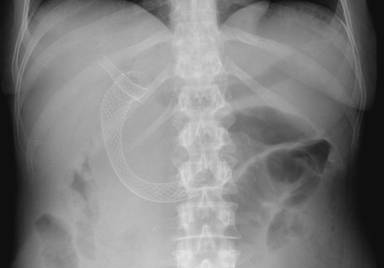

Upper endoscopy had previously shown duodenal stenosis due to circumferential ulcerated and infiltrative lesions in all cases. Facing a high probability of an unsuccessful ERCP, we discussed the possibility of endosonography-guided biliary drainage and duodenal stenting with the surgical and oncological teams. We performed the procedure following the same sequence in all cases. For the whole procedure, the patient was under general anesthesia and fluoroscopic guidance was used. A therapeutic duodenoscope (TJF-160, Olympus, Tokyo, Japan) was introduced and advanced until the duodenal bulb. A 0.035 guidewire (Jagwire®, Boston Scientific, Natick, MA, USA) was advanced through the duodenal stenosis until the proximal jejunum (Figure 1). The stenosis was dilated with a dilation balloon (CRETM Balloon Dilator, Boston Scientific, Natick, MA, USA) until 15 mm. The duodenoscope was advanced but the major ampulla could not be identified. The guidewire was left in place and the duodenoscope was removed. A linear array echoendoscope (GF UCT-140, Olympus, Tokyo, Japan; Alfa 5 processor, Aloka, Tokyo, Japan) was introduced. Endosonography examination was performed to look for the dilated common bile duct, the largest left intrahepatic duct and the presence of collateral veins. In all cases, the largest left intrahepatic ducts were smaller than 6 mm and we did not attempt the antegrade transhepatic access. The common bile duct was punctured with a 19-gauge needle (EUSN-19T, Cook Medical, Bloomington, IN, USA) (Figure 2). Bile was aspirated and contrast was injected to confirm an adequate position of the needle (Figure 3). After confirmation with fluoroscopy, a 0.035 guidewire (Jagwire®, Boston Scientific, Natick, MA, USA) was advanced through the needle into the common bile duct and the needle was retrieved. A 6-Fr cystotome (Endo Flex, Voerde, Germany) was then inserted over the guidewire to create a bilioenteric communication (Figure 4). In four patients, a partially covered biliary self-expandable metallic stent (WallFlex® 60/100 mm, Boston Scientific, Natick, MA, USA) was inserted into the common bile duct and successfully deployed, creating a choledochoduodenal fistula (Figure 5). In one patient (Patient#2), we deployed an uncovered biliary metallic stent (WallFlex® 60/100 mm, Boston Scientific, Natick, MA, USA). The echoendoscope was removed and the duodenoscope was introduced over the duodenal guidewire. A non-covered duodenal self-expandable metallic stent (WallFlex® 120/220 mm, Boston Scientific, Natick, MA, USA) was inserted over the guidewire and deployed in all patients (Figures 6 and 7).

Figure 6. Deployed biliary and duodenal stents. |

Figure 7. Deployed biliary and duodenal stents (X-ray). |